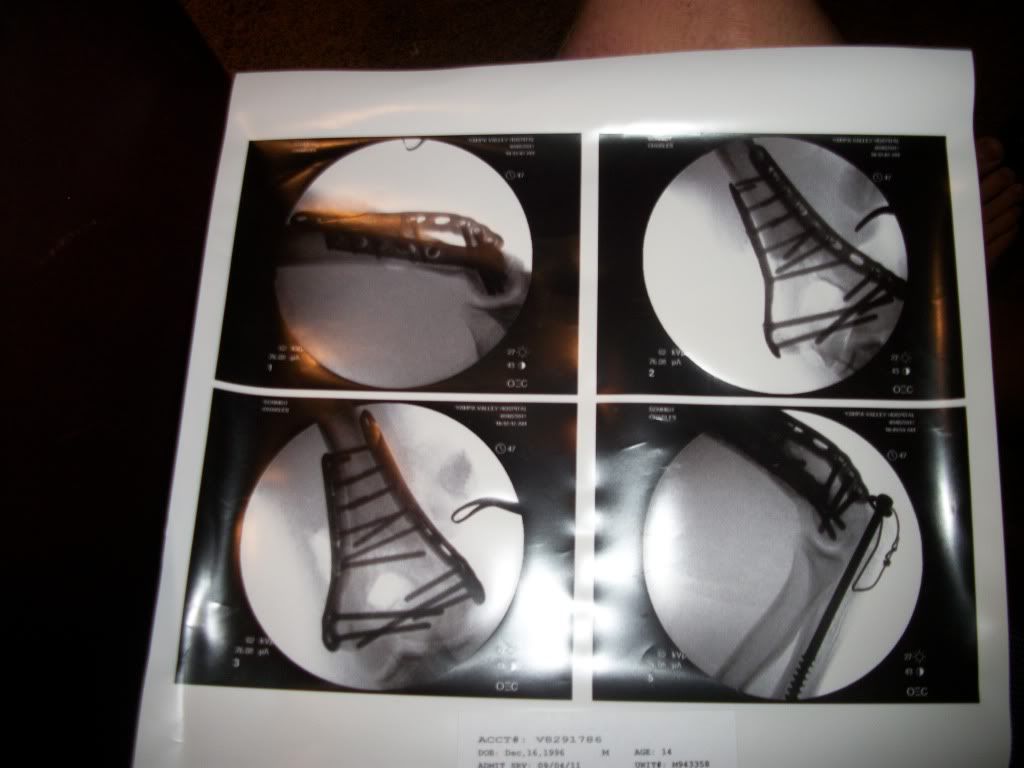

Yesterday on my birthday, I was doing a dub misty 9 on my tramp, underrotated, and snapped my ankle on landing. I displaced a fragment of my tibia and it cut the cartilage on my joint, and may have damaged my growth plate, so later today I am getting surgery on my ankle to repair the cartilage, as well as getting screws in to fix my tibia. My recovery time is 6 months and for the second year in a row I will not be able to spend my summer actively, as I broke my wrist and arm last year. So I need things to do over the summer, what ideas do you have NSG? And yes the first thing I said when I landed was my ankle is broken. Excuse my poor grammar or spelling as I am on a morphine drip and in pain.